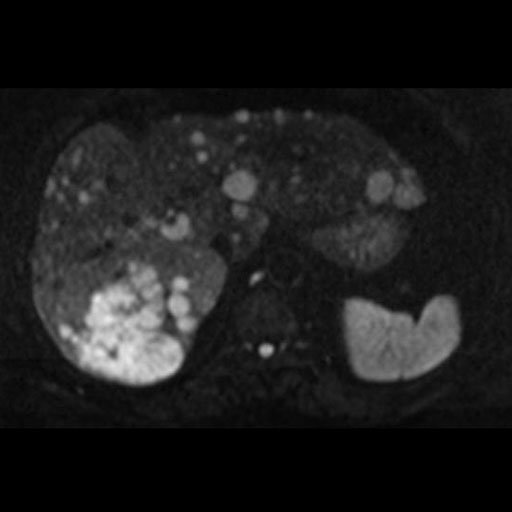

|

Free breathing syngo REVEAL with 2D PACE

provides improved image quality in abdomen imaging |

Malignant infiltration of iliac lymph nodes,

seen with syngo REVEAL |

Pancreatic cancer detected by syngo Reveal |

Coronal MPR of a whole-body DWI examination in

case of multiple myeloma (right b=50 mm/s2 image left ADC map |